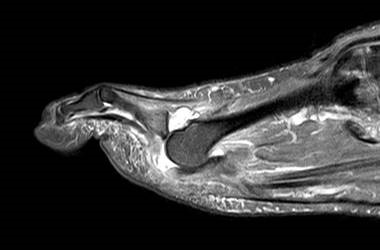

Die Überbelastung des Metatarsale II und III im distalen Bereich äußert sich in Druckschmerzen und Schwielenbildung plantar unter den Metatarsale II und III Köpfen (Abb. 1). Auch degenerative Veränderungen der plantaren Kapsel und der plantaren Platte der Metatarsophalangealgelenke treten auf, was zu einer Insuffizienz der Grundgelenke mit Subluxation oder Luxation der Kleinzehen führt (Abb. 2 und 3).